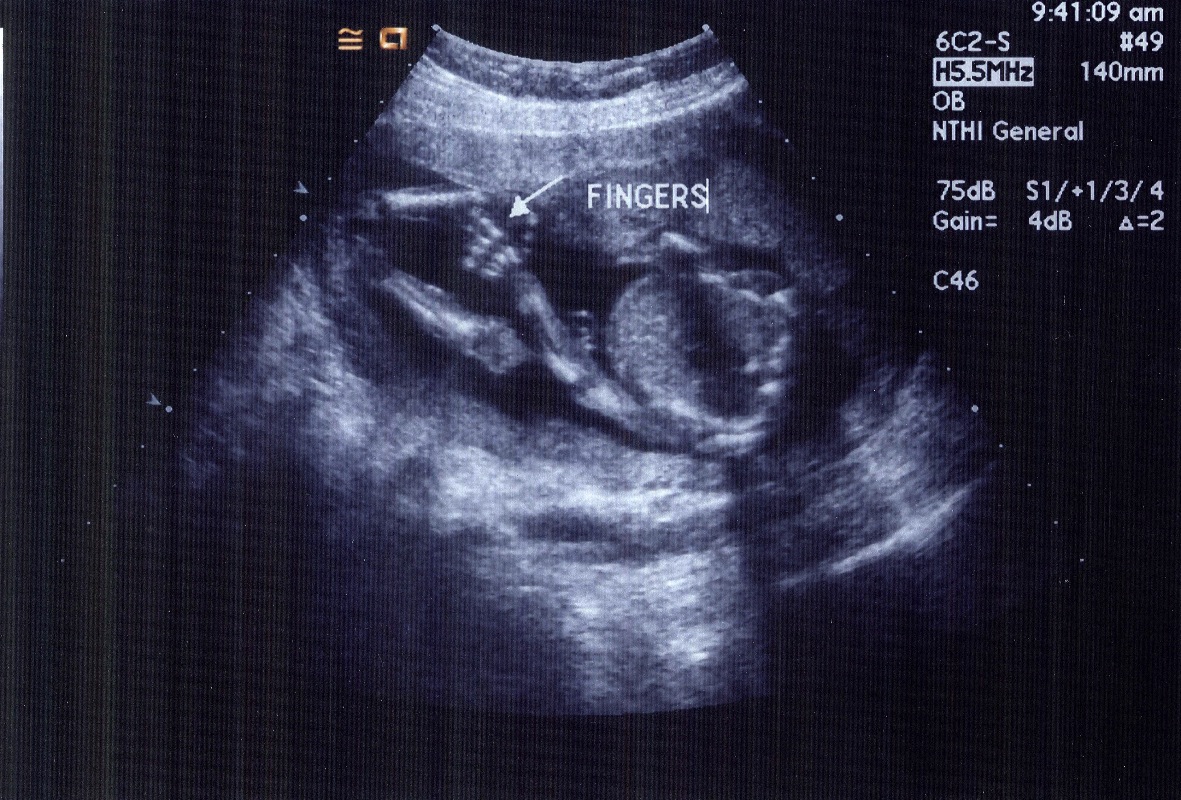

It's a Girl!